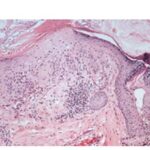

Histopathology

Actinic keratoses are keratinocytic dysplasias or squamous cell carcinomas in situ. This definition is preferable to their designation as precancerous because most of them never progress to cancers. Biologically, the lesions are still benign; invasion into the dermis, if present at all, is limited to the most superficial portion, the papillary dermis (see Differential Diagnosis) . |

This variety of keratosis, sometimes referred to as florid keratosis, may easily be overdiagnosed as invasive squamous cell carcinoma by the unwary. Mild or moderate papillomatosis may be present. The epidermis is thickened in most areas and shows irregular downward proliferation that is limited to the uppermost dermis and does not represent frank invasion .A varying proportion of the keratinocytes in the stratum malpighii show a loss of polarity and thus a disorderly arrangement. Some of these cells show pleomorphism and atypicality (“anaplasia”) of their nuclei, which appear large, irregular, and hyperchromatic. Often the nuclei in the basal layer are closely crowded together. Some of the cells in the midportion of the epidermis show premature keratinization, resulting in dyskeratotic cells or apoptotic bodies characterized by homogeneous, eosinophilic cytoplasm with or without a nucleus. In contrast to the epidermal keratinocytes, the cells of the hair follicles and eccrine ducts that penetrate the epidermis within actinic keratoses retain their normal appearance and keratinize normally. Occasionally, cells of the normal adnexal epithelium extend over the atypical cells of the epidermis in an umbrella-like fashion. In some cases, abnormal keratinocytes extend downward on the outside of the follicular infundibulum to the level of the sebaceous duct and, less commonly, along the eccrine duct . |

A variant of the hypertrophic type of actinic keratosis is the lichenoid actinic keratosis, which demonstrates nuclear atypia, irregular acanthosis and hyperkeratosis, the presence of basal cell liquefaction, degeneration of the basal cell layer, and a bandlike “lichenoid” infiltrate in close apposition to the epidermis . Fairly numerous eosinophilic, homogeneous apoptotic bodies are seen in the upper dermis as so-called Civatte bodies. Aside from the presence of nuclear atypicality, |